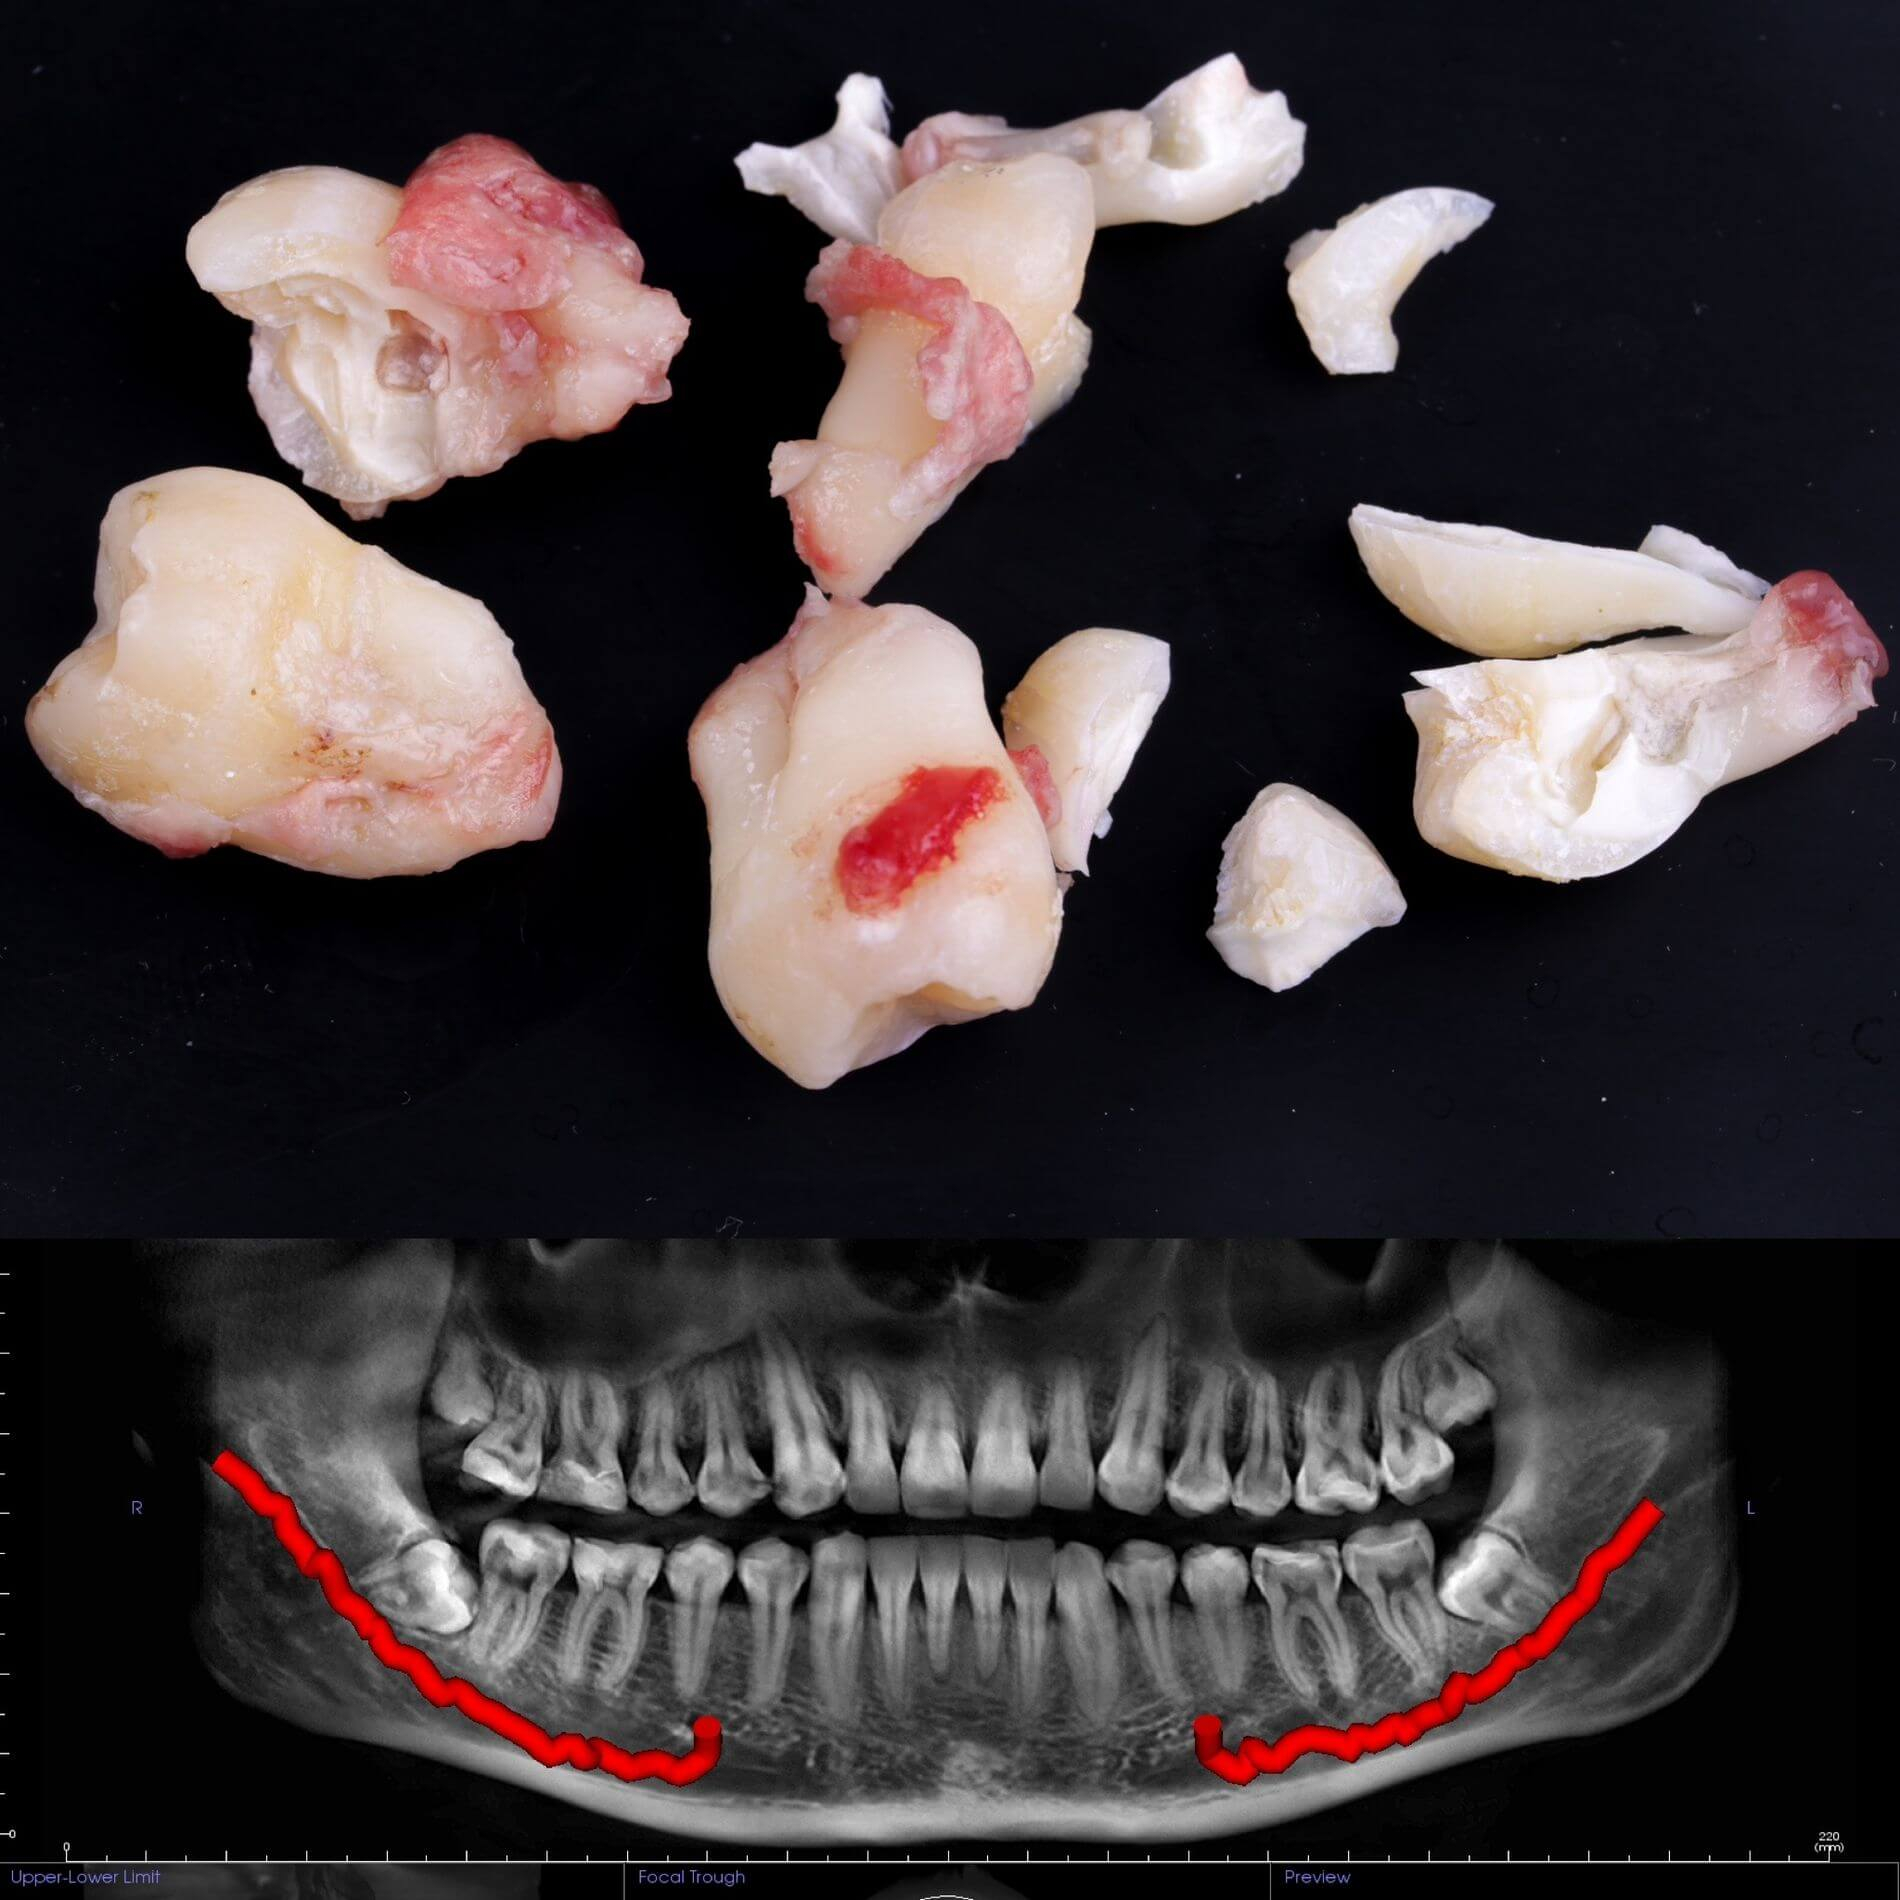

Види видалення зубів мудрості

- Окреме видалення коронки зуба та його коренів - якщо зуб прорізаний і корені ростуть по окремо.

- Видалення зуба за схемою 1 або 2 із розрізом ясна - якщо зуб прорізаний частково.

- Розріз ясна, звільнення зуба від прилеглої кістки ультразвуком та видалення за схемою 1 або 2 - якщо зуб не прорізався, але турбує.

Вирвати зуб мудрості у Львові можна простіше, ніж тобі здається, в Космічній стоматології Драганчука. Почни цей шлях з простого кроку - первинної зустрічі з хірургом-стоматологом. На консультації ми зробимо основне – скеруємо тебе на 3D комп’ютерну томографію, щоб врахувати близькість нижньощелепного нерва (нижні 8-ки) та верхньощелепної пазухи (верхні 8-ки) та складемо план видалення зубів.

Галерея